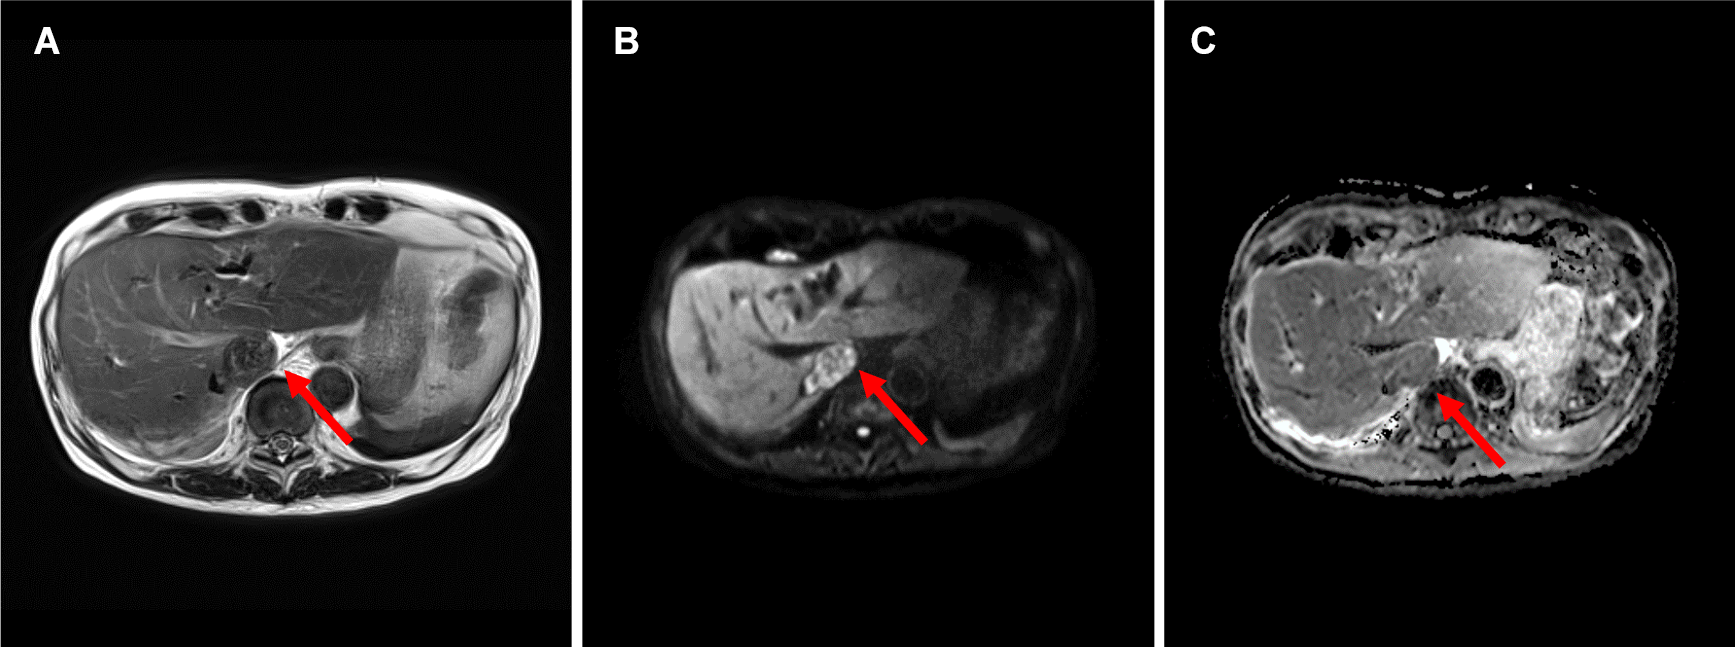

図2.ガドビスト造影MRI (A:T2WI B:DWI(b=800) C:ADCmap D:造影前脂肪抑制T1WI E:造影後脂肪抑制T1WI F:造影後True FISP G:造影後TrueFISP冠状断像)

(A-F→)下大静脈内の腫瘍はT2WI低信号で、DWIで不均一な高信号、ADCは軽度低下している。hypovascularであり、造影True FISP冠状断像で頭側は右房内(➤)、尾側は右腎静脈起始部(⇒)、左腎静脈(➔)に及んでいることがわかる。